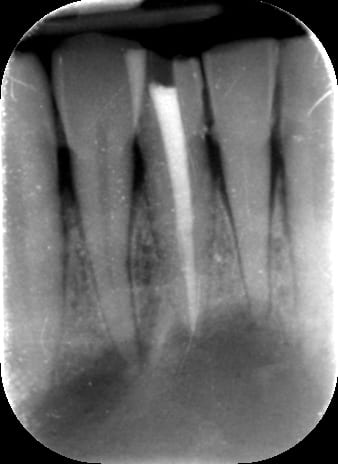

Si bien entendu endo faite après séance CaOH à J-7 et obturation à J-2.

Le but de ma question était de savoir si on peut être sûr que l'obturation endo a été réalisée dans de bonnes conditions : taille gigantesque de lésion périapicale, 6 jours de Ca(OH)2, risque de suintement lors de l'obturation ?

Si j'avais dû traiter ce cas, je pense que j'aurais fait une obturation à rétro pour minimiser le moindre risque.

je suis pas expert en endo, mais je vais donner mon avis ( qui est celui de stéphane aussi il me semble ), une obturation à retro non si l'endo a été faite dans les règles de l'art, mais par contre si tu as un doute tu peux faire une résection apicale.

vu que l'endo est récente et faite en principe dans les règles de l'art, l'obturation à rétro n'a pas d'intérêt dans ce cas.

comme le dit mac, une simple résection apicale à minima permet d'éliminer la partie terminale qui comporte le delta apical dont certains canalicules ne sont pas forcément obturés correctement.